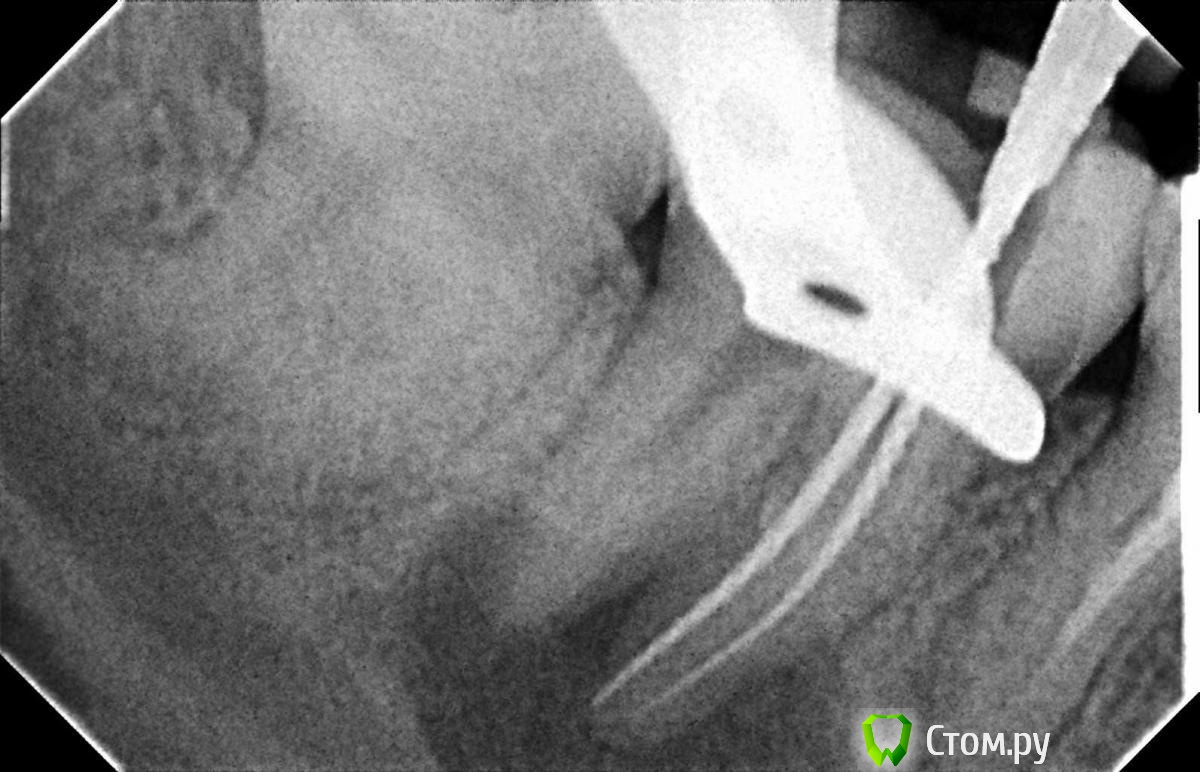

Л Ю С Я Опубликовано 10 января, 2014 Поделиться Опубликовано 10 января, 2014 .Новый кейс-совсем свежий пока без долгосрочного результата.Пациентка попала случайно удаляла зуб 28 и хирург сделал ОПТГ,где стали видны обширные периапикальные процессы в области 37 47.Побывав у меня на консультации и услышав план лечения и стоимость,пациентка решила видимо полечить подешевле.,побывав на консультациях в нескольких клиниках и в итоге даже попала к главному стоматологу нашей области. Все ей сказали что удаление онли. Вернулась,-засада была в том что план я писал исходя из ОТПГ не сделав прицел(виноват),сделав прицел понимаю что все сложнее чем я думал-ну что же тем интереснее.Переписав план лечения и подняв ценник на 40%(пациентке не оставалась выбора),начали лечение.1-посещение-ревизия пломбы.понимаю что кто то до меня с маниакальным упорством пытался запломбировать мезиальный язычный канал каналонаполнителями. Убрал два фрагмента из верхней трети мезиального язычного.2-посещение еще фрагмент из мез язычного плюс немного с дистальными поработал(их оказалось два сплит в верхней трети)3-визит обошел фрагмент в мезиальном щечном и доработал остальные каналы.4-визит -паковка.На предпоследнем снимке видны поры-допаковал(просто на финальном не очень видно)Класс! Ждем рекол через 6 месяцев. Паковка чем? Сквирт? Ссылка на комментарий

Hans85 Опубликовано 10 января, 2014 Автор Поделиться Опубликовано 10 января, 2014 Не чистый сквирт-скорее гибрид не знаю как правильно назвать -в общем сначала сквирт а затем дополнительно разогрев плаггером и уплотнение.Просто аппарат для сквирта пока не айс(Бифилл) ну вот клинику откроем там будет по фен-шую - ГуттаИзи. Ссылка на комментарий